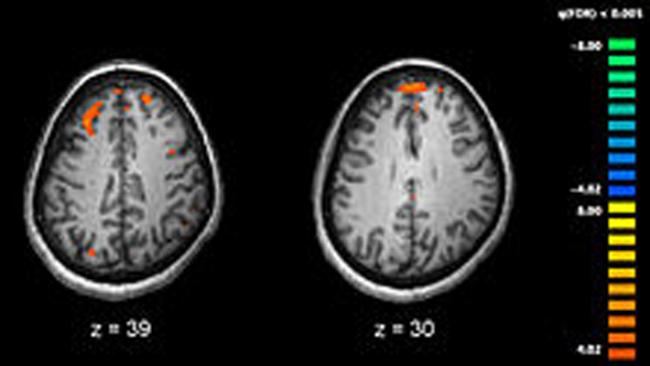

“At this stage, we discovered critical malformations in the cortex of the mini-brains formed from the iPSCs of the patients with schizophrenia,” said Stachowiak. That made sense, he added, since increasing evidence has recently linked schizophrenia to abnormal functioning in the cortex, the largest part of the brain, which is responsible for such critical functions as memory, attention, cognition, language and consciousness.

They found that certain kinds of neural progenitor cells (which later become neurons) were abnormally distributed in the cortex of the mini-brains developed from patients. And while maturing neurons were plentiful in regions outside of the cortex, they were rare in the cortex, Stachowiak explained.

“Our research shows that the disease likely starts during the first trimester and involves accelerated cell divisions, excessive migration and premature differentiation of the neuroectodermal cells into neurons,” he continued. “Neurons that connect different regions of the cortex, the so-called interneurons, become misdirected in the schizophrenia cortex, causing cortical regions to be misconnected, like an improperly wired computer.

“We now can state that schizophrenia is a disorder of faulty brain construction that occurs early in development, corresponding to the first trimester, and involving specific malformation of neuronal circuits in the cortex,” he said. The experiments implicate the dysregulation of the INFS mechanism as a trigger for deconstructing gene networks in the developing brain cells of individuals who will later develop the disease.